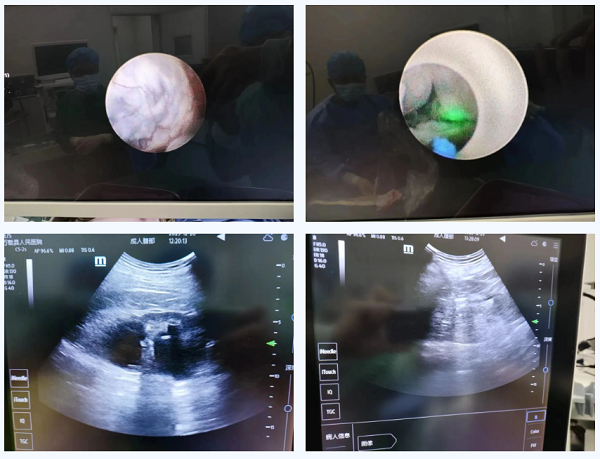

经过泌尿外科团队的精心准备,采用B超引导下,先行经皮肾钬激光肾结石碎石取石术,再在肾镜下用钬激光切开囊肿行肾囊肿去顶术治疗。术后,袁大哥已痊愈出院,其对手术效果非常满意。

术前术后对比图